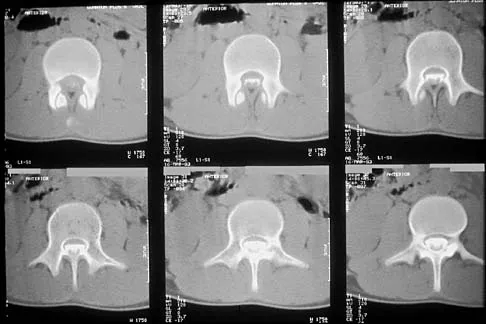

Figures 27a through 27c show the radiographs and CT scan of a 27-year-old man who sustained a low-velocity gunshot wound to the neck. He is quadriplegic (ASIA A), hemodynamically stable, and does not have drainage from his wound. After initial resuscitation and stabilization, the cervical spine and spinal cord injuries are best managed by

Explanation

Although the spinal canal has been penetrated, the lateral masses are intact bilaterally with only partial destruction of the vertebral body and penetration of the lamina on one side, thus the cervical spine is not unstable and surgical stabilization is not indicated. Dural repair is not indicated since there is no external cerebrospinal fluid leakage. Surgical treatment should be based on the need to treat extraspinal pathology only. Bono CM, Heary RF: Gunshot wounds to the spine. Spine J 2004;4:230-240.